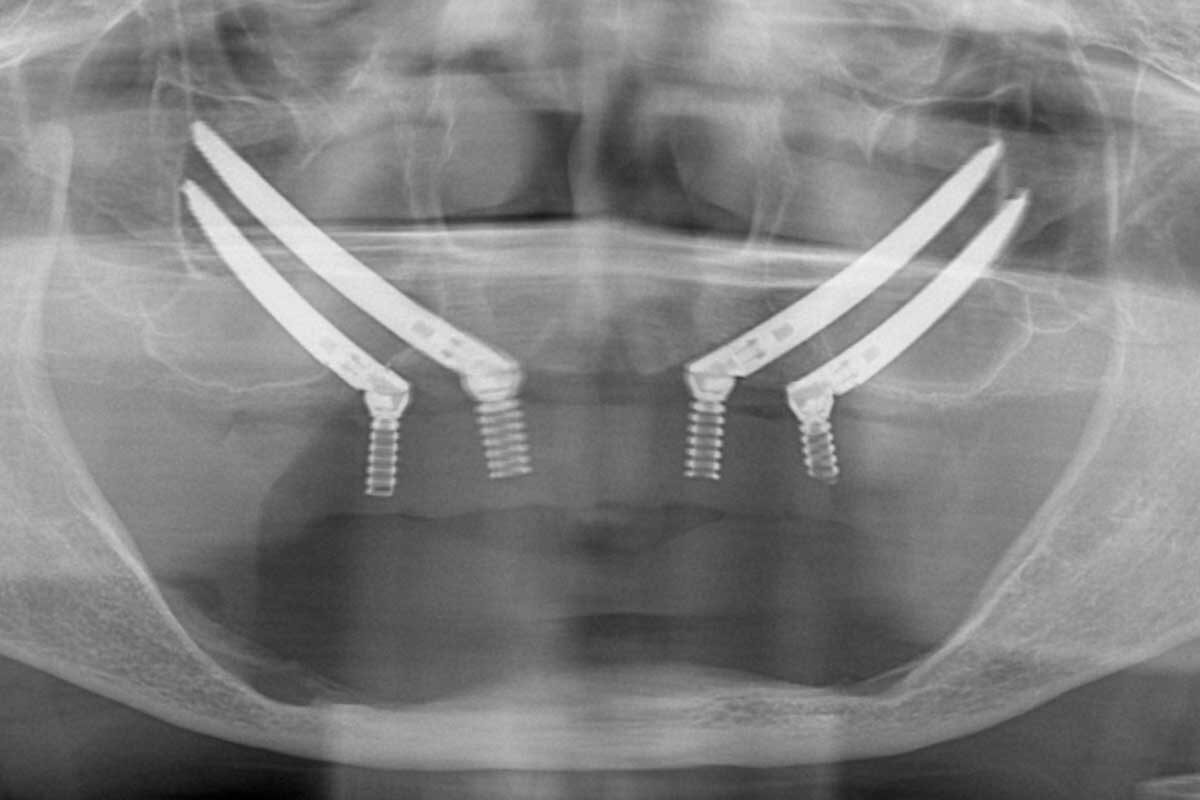

この患者さんの術前のパノラマX線画像ですが、昔ボクシングをされていたそうで上顎の歯をほぼ全てなくしていました。どこの歯科医院にいっても「上顎の骨がないから入れ歯しか施術できない」と言われたそうです。まだ若かったこともあり、入れ歯自体を受け入れることができなかったそうです。手術前に麻酔専門の医師が静脈鎮静麻酔を行います。この麻酔法により緊張感や恐怖心はなくなり、鎮静剤の点滴を行いながらリラックスした状態で手術が受けられます。しかも、入院の必要はなく、処置が終了すればその日に帰宅できます。

手術日当日 術中

手術開始です。患者さんからすると「怖い」「痛そう」と感じると思いますが、実際は静脈鎮静麻酔によりリラックスしているのと併せて、局所麻酔薬も使用するので痛みは感じないです。この患者さんの治療計画は

上顎:Extra Maxillo Zygomatic All-on-4 ( EZ4 )

下顎:All-on-4 ( オールオン4 ) でした。

上顎は4本だけのザイゴマインプラントで オールオン4 を完成させます。下顎は4本のインプラントを角度をつけてバランスよく配置します。

この手術計画だと通常は4時間くらいの手術となります。

術後ですが静脈鎮静麻酔なので意識が聡明になるのがとても早いです。小休憩後に足取りがしっかりしているのを確認して術後のパノラマX線画像を撮影します。インプラントが適正な位置に施術できているかを確認します。術前が上下、左右ともに噛み合わせのバランスが崩れていましたので、出来るだけ噛み合わせが自然なポジションになるようにインプラントを配置しました。オールオン4インプラントやザイゴマインプラントの全てを45N・m以上の高トルクで締結されています。